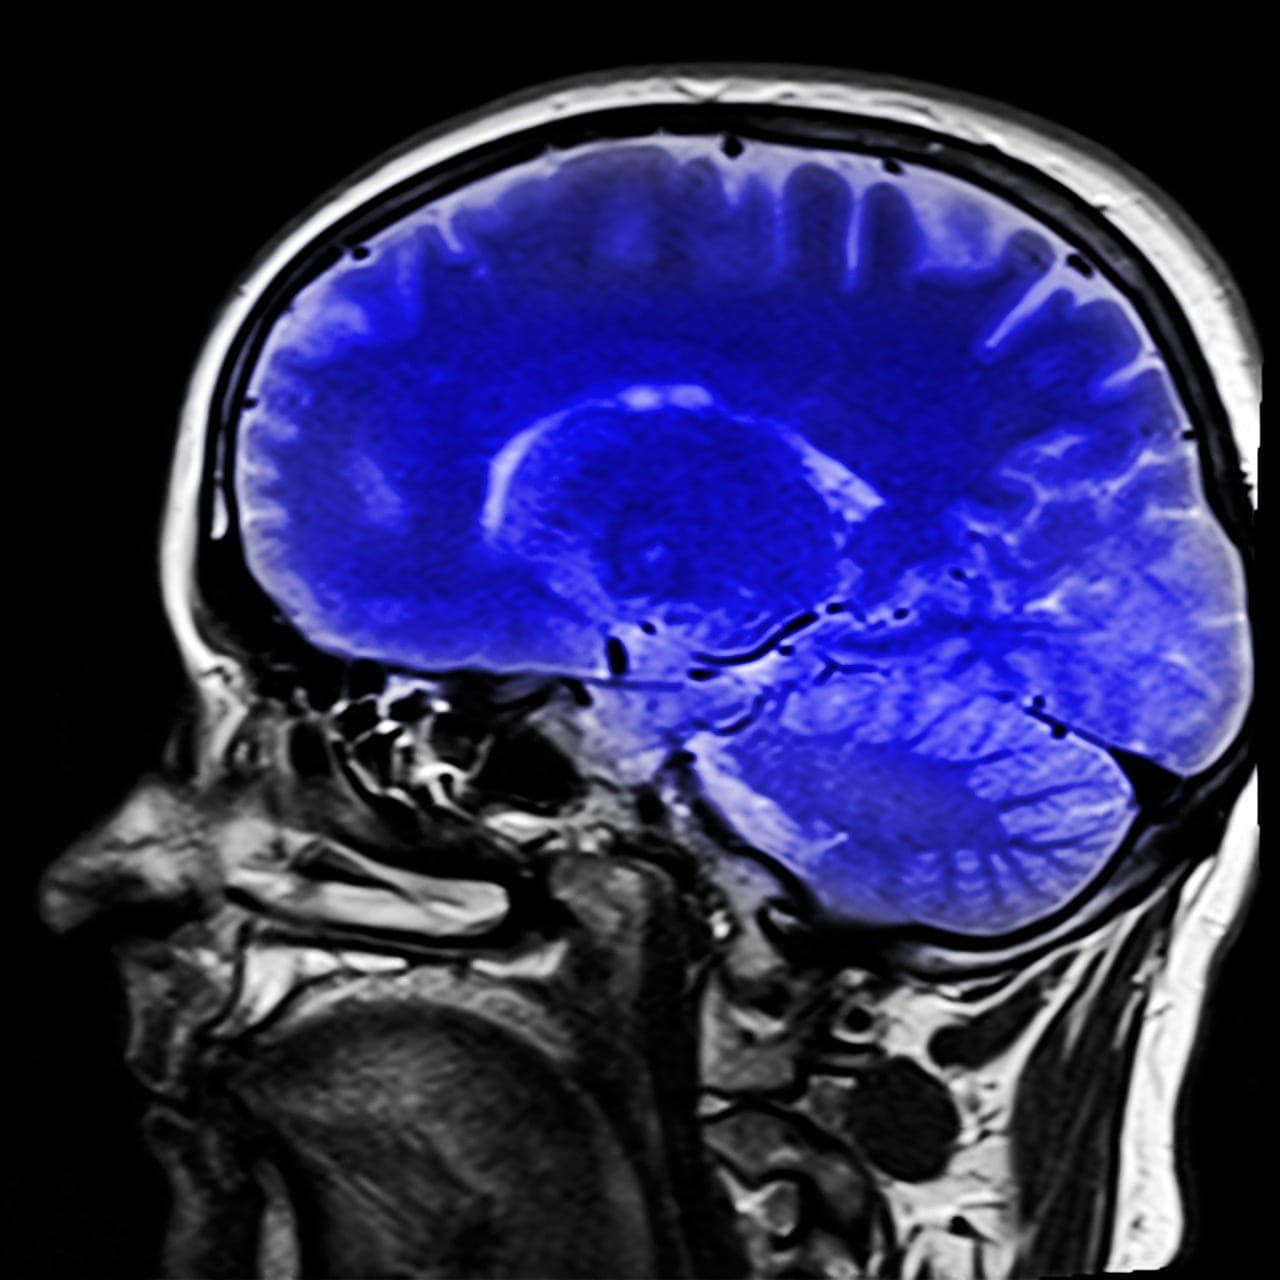

Comme l’explique à Futura Charlie Demené, maître de conférences à l’ESPCI Paris-PSL et chercheur au Laboratoire physique pour la médecine de Paris, la mise au point de cette innovation a été complexe. Le principal problème ? L’os crânien ! Sa taille vient entraver l’imagerie ultrasonore. Sa structure absorbe et modifie la propagation des ultrasons. Le faisceau ultrasonore envoyé subit des distorsions ce qui rend impossible une reconstruction de l’image.

Les chercheurs ont finalement utilisé des microbulles fluorescentes. Elles ont un diamètre de deux microns et sont enveloppées dans une bicouche lipidique spécialement conçue pour la pratique clinique. Ces microbulles passent dans la vascularisation et se répandent de façon à être isolées. A leur contact, les ultrasons sont réfléchis, ce qui crée une onde sphérique qui repasse à travers le crâne et permet de mesurer précisément la distorsion qu’induit l’os. Elles sont très facilement localisables.

Cette technologie pourrait permettre de mieux surveiller les anévrismes, comprendre ce qui les déclenche, mieux prévenir et mieux traiter cette pathologie.